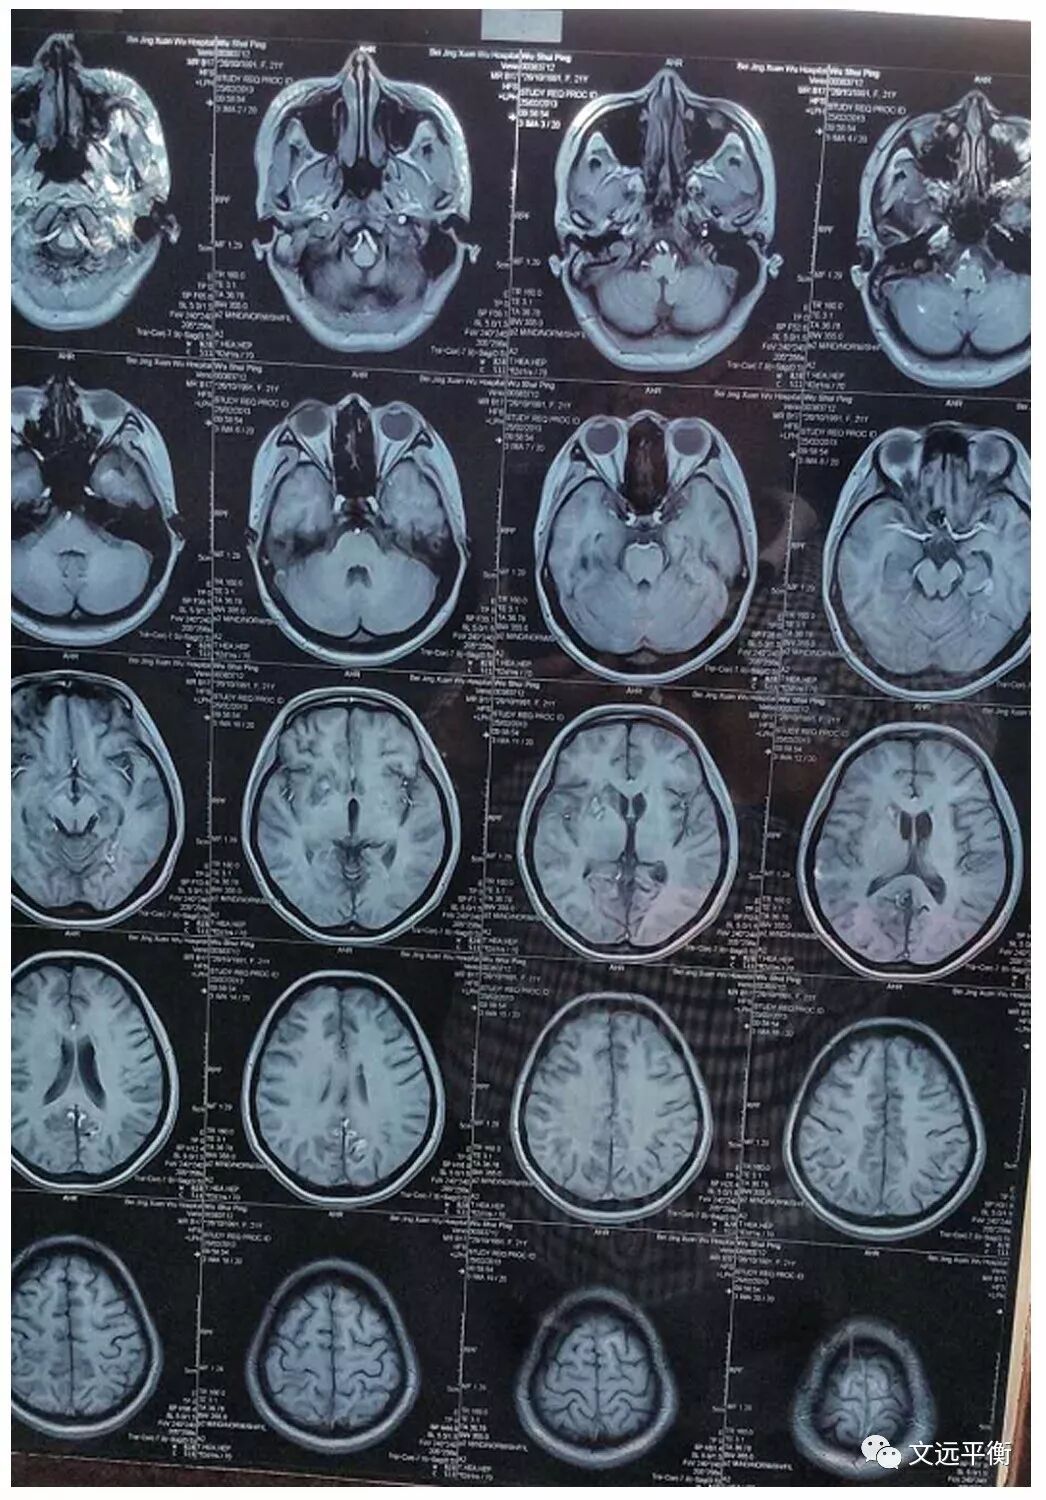

影像资料对比:图一、二。MRI平扫+增强+灌注扫描(2013.2.25宣武医院)报告提示:脑内多发异常信号,梗死伴渗血?血管炎?右侧乳突炎)

图三头颅MRV报告(2013.2.25宣武医院)提示:未见异常。

图四、五:复查颅脑MRI(2016.7.13龙岩市第二医院)提示:右侧基底节区,左枕叶.右侧额叶多发软化灶并周围胶纸增生,右侧额骨术后改变?